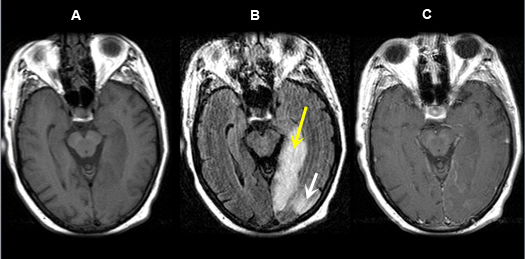

Figure 5 A-C: MR Images

Posterior cerebral artery territory Acute Stroke

Case 5:

Imaging findings: Figure 5 A-C

- Pre-contrast axial T1 wtd. MRI

- Axial flair image

- Post-contrast axial T1 wtd. MRI

Acute infarction is seen involving the left occipital lobe (yellow arrow) and adjacent left temporal lobe (white arrow). The left posterior cerebral artery territory infarction is better seen on flair sequence (Fig. B) than on T1 wtd. pulse sequence (Figs. A, C).